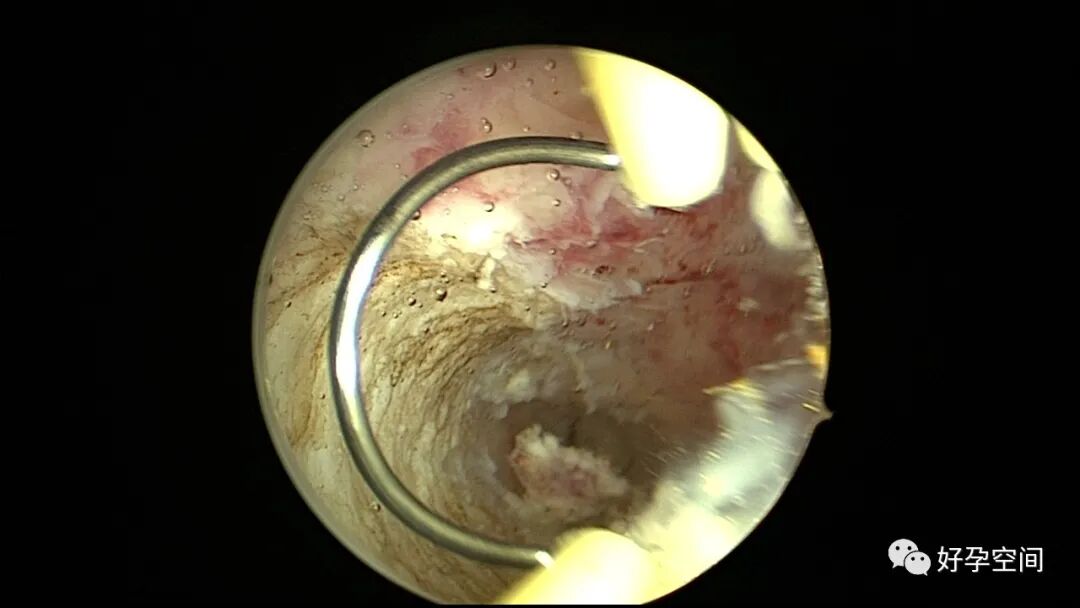

病例2:患者31岁,原发不孕,2019年11月在重庆某妇幼保健院做宫腹腔镜手术疏通输卵管,术中未取内膜活检,术后未孕。2021年7月在成都某大型生殖中心试管怀孕双胎(移植前未做宫腔镜检查及内膜活检),2021年11月孕4月双胎破水,在达州当地医院引产清宫,清宫术后40天复诊B超提示宫腔胚物残留。2022年1月到我院(眉山蕴缨妇产医院)行宫腔镜手术切除残留组织,2022年4月宫腔镜术后3个月复诊B超提示宫腔粘连,再次来我院行宫腔镜分粘。宫腔被覆一层沙丘状质脆增生组织,宫腔下段两侧壁内聚,行分粘术,取内膜送病检。

子宫内膜结核是由结核分枝杆菌在子宫内膜部位种植引起的炎症,是仅次于输卵管结核的常见女性生殖器结核。子宫内膜结核常由输卵管结核蔓延而来,多继发于盆腔腹膜结核或肺结核。子宫内膜结核的超声表现主要为:子宫内膜回声不均匀、宫腔内结节样病灶、宫腔内强回声灶、单纯的子宫内膜薄等。盆腹腔超声显示输卵管炎性表现:输卵管增粗、肥厚、扭曲、僵硬、输卵管积液积脓、卵巢旁混合性包块、输卵管系膜囊肿、盆腔包裹性积液等。术中所见:盆腹腔组织粘连、盆腹腔粟粒样结节、结核球、脓肿等,输卵管伞端烟斗样外翻,输卵管内充满淡黄色干酪样或豆渣样组织。宫腔镜显示宫腔狭窄、宫壁僵硬、宫内膜肉芽肿样增生、内膜质脆易刮除、干酪样组织、脓液等。

温宝宁等将子宫内膜结核宫腔镜检查的镜下表现分为:①宫腔形态、大小正常,双侧输卵管开口可见,子宫内膜发红、增厚,局部突起,表面可见少量质脆的小颗粒状赘生物,可刮出质脆的子宫内膜组织;②宫腔形态正常,但是宫腔内无正常子宫内膜,均被覆一层苍白的绒毛状或棉絮状质脆组织,血管少,无异形血管,宫腔内病灶与正常组织分界明显;③宫腔形态异常,呈窄桶状,子宫内膜瘢痕化,输卵管开口细小,甚至宫角消失。